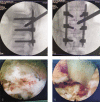

Interventions: The patient underwent PPSF at the level of T12 to L2, but her neurological function did not fully recover after the operation. One week after the injury, we performed TESCD on her.

Outcomes: There was an immediate improvement in her neurological function in just 1 day after 2-stage operation. During the 6-month follow-up period, her neurological functions gradually recovered, and she was able to defecate and urinate. At the last follow-up visit, her spinal cord function was assessed to be at Frankel grade D.

Lessons: PPSF plus TESCD can achieve complete spinal cord decompression, promote neurological recovery, and is therefore an effective method for the treating lumbar burst fractures with severe neurologic deficits.